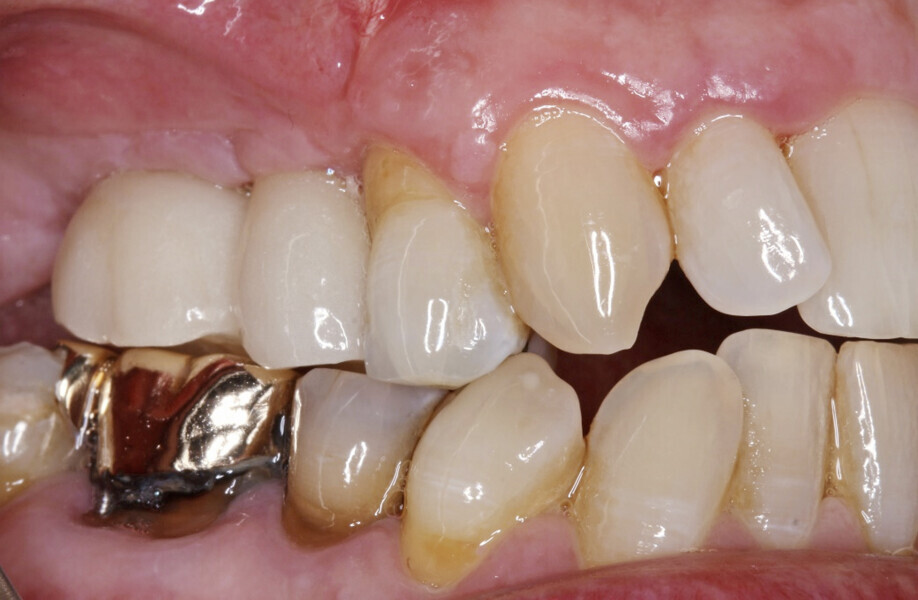

A digital impression using an intra-oral scanner (Primescan) was then captured using the Atlantis IO FLO for a digital restorative workflow (Fig. 13). An Atlantis CustomBase solution, consisting of an Atlantis crown, an Atlantis abutment and an Atlantis abutment screw, was fabricated for each implant and tried in, and no adjustments were needed (Figs. 14 & 15). After seating, a radiographic evaluation was performed to verify the final restorations (Fig. 16). The final restorations showed excellent soft-tissue adaptation and an aesthetic outcome (Figs. 17 & 18). The patient was extremely satisfied with the outcome of the treatment and the fixed restorations.

Fig. 17: Screw access holes sealed and amalgam in tooth #14 replaced with composite.

Fig. 18: Final restorations in situ.